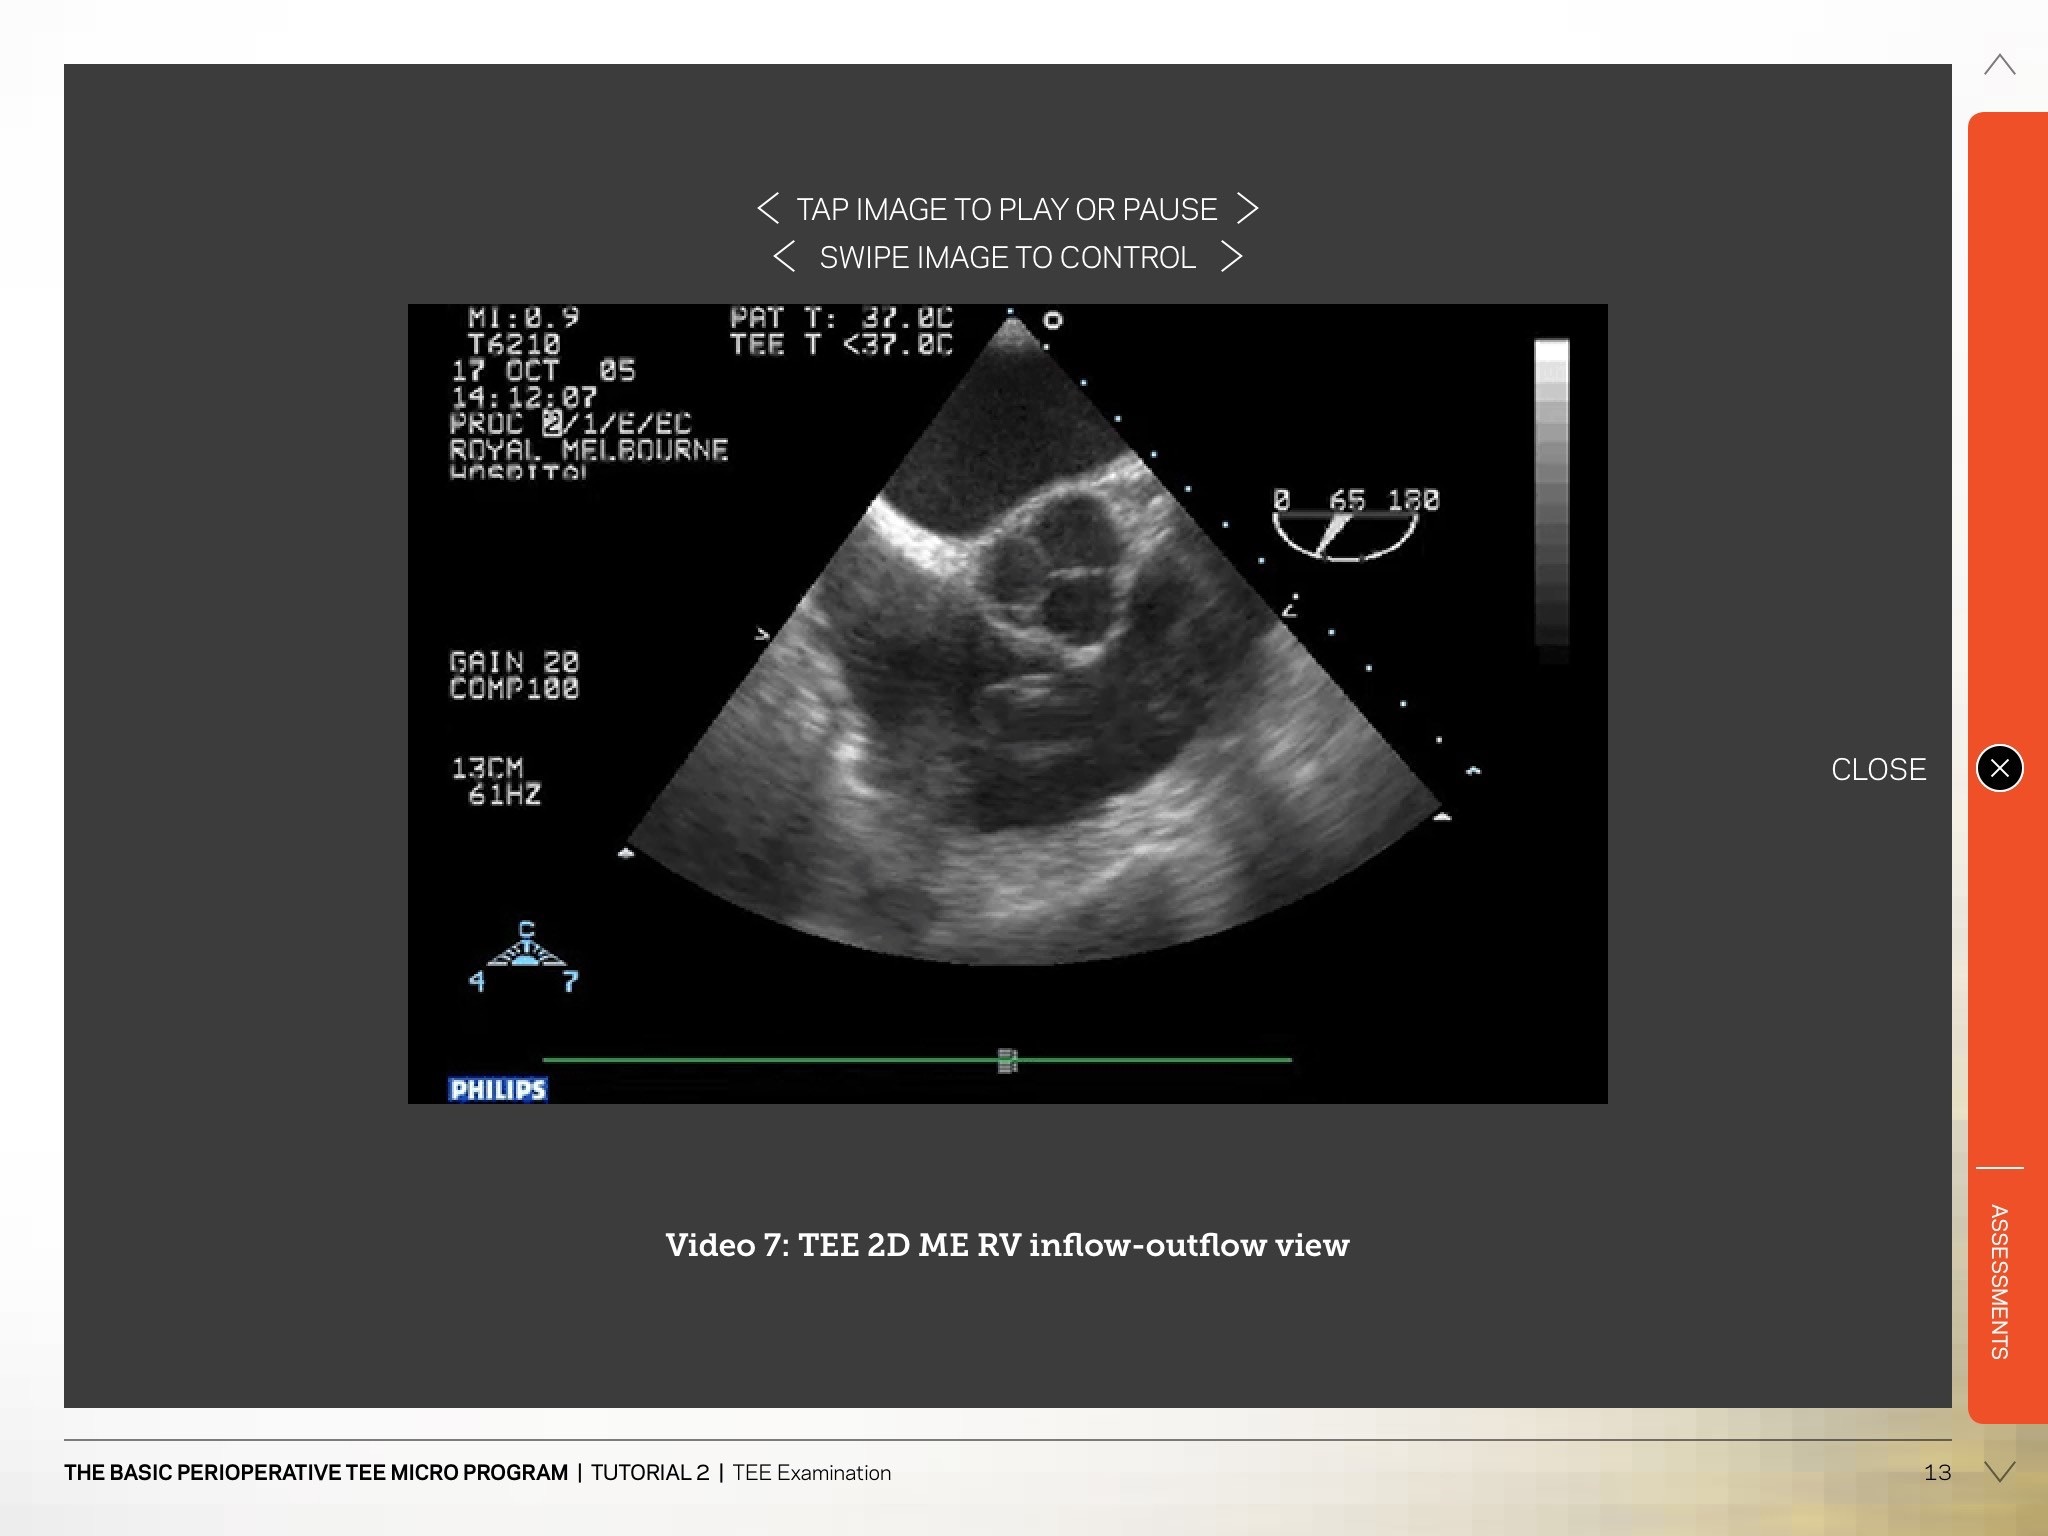

The Heartweb app has been designed to deliver custom online education courses. Our courses teach clinical ultrasound and echocardiography to health professionals worldwide. The app will allow students to read their course materials via a tablet. The e-learning courses allow the student the flexibility to study in their own time and place. Existing students will log into the app and will be able to gain access to the relevant course materials. Content within the HeartWeb app is proprietary curriculum material for and only available to enrolled students. Heartweb Pty Ltd is an established, international, commercial provider of online higher education.